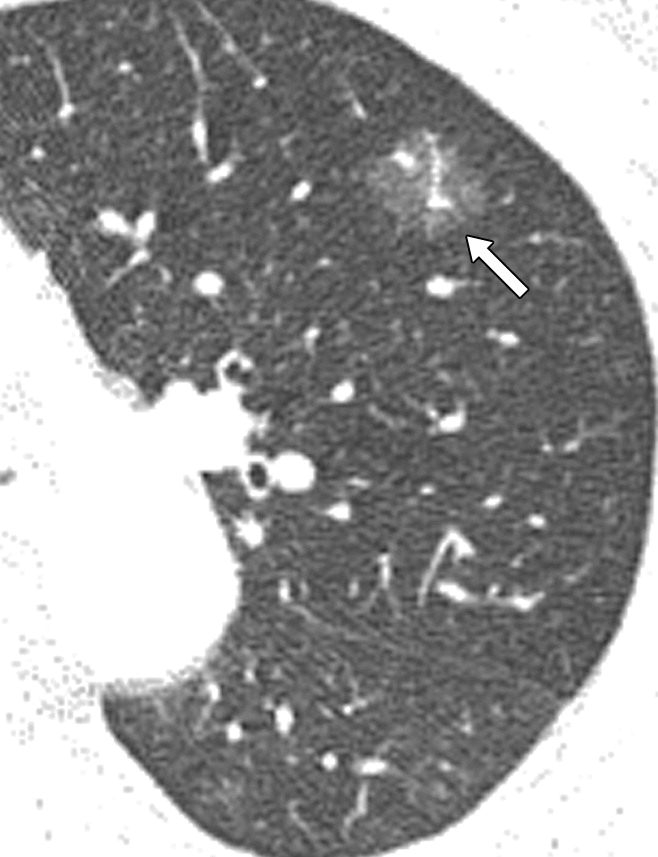

肺部磨玻璃影是从微小逐渐生长至较大的,不会一开始就变成巨大肿瘤。在初期(直径小于1厘米),它们通常呈现为纯度较高、密度较低、边缘清晰,此时尚未明确为恶性,可称为纯GGO。经过切除后,多数情况下被证实为腺瘤样不典型增生(AAH,癌前病变),或者是原位腺癌(AIS,无周围血管间质侵犯,不会转移,5年生存率100%),甚至极少数情况下可能是微浸润腺癌(MIA,周围血管间质侵犯距离小于5毫米,也不会转移,切除后,5年生存率100%)。

随着结节逐渐增大和恶化,可能会引起实性成分增加,变得不那么纯粹,称为混合性GGO。有时,还会出现分叶、毛刺、空泡,胸膜凹陷,血管密集等改变,这时多数已经是恶性了,称为浸润性腺癌。这种情况下,肿瘤可能进入人体血管,发生肺内或全身转移。